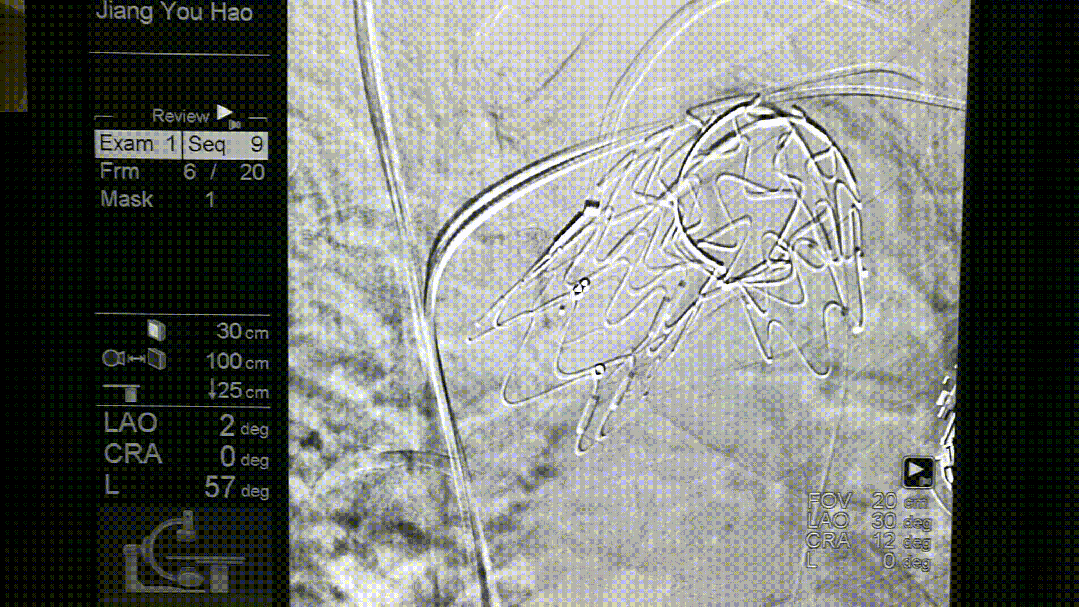

导丝破膜,各角度反复确认

转播手术过程中即便熟练团队开窗,时间不可控,导丝穿破FUSTAR

我们在两头35kg巴马公猪中完成动物实验:

成功实现弓上分支的快速、准确原位开窗;

破膜过程流畅,无分支或主动脉损伤;

取出标本可见圆形破口、支架贴合良好,证实技术可行性。

动物实验

巴马公猪35kg